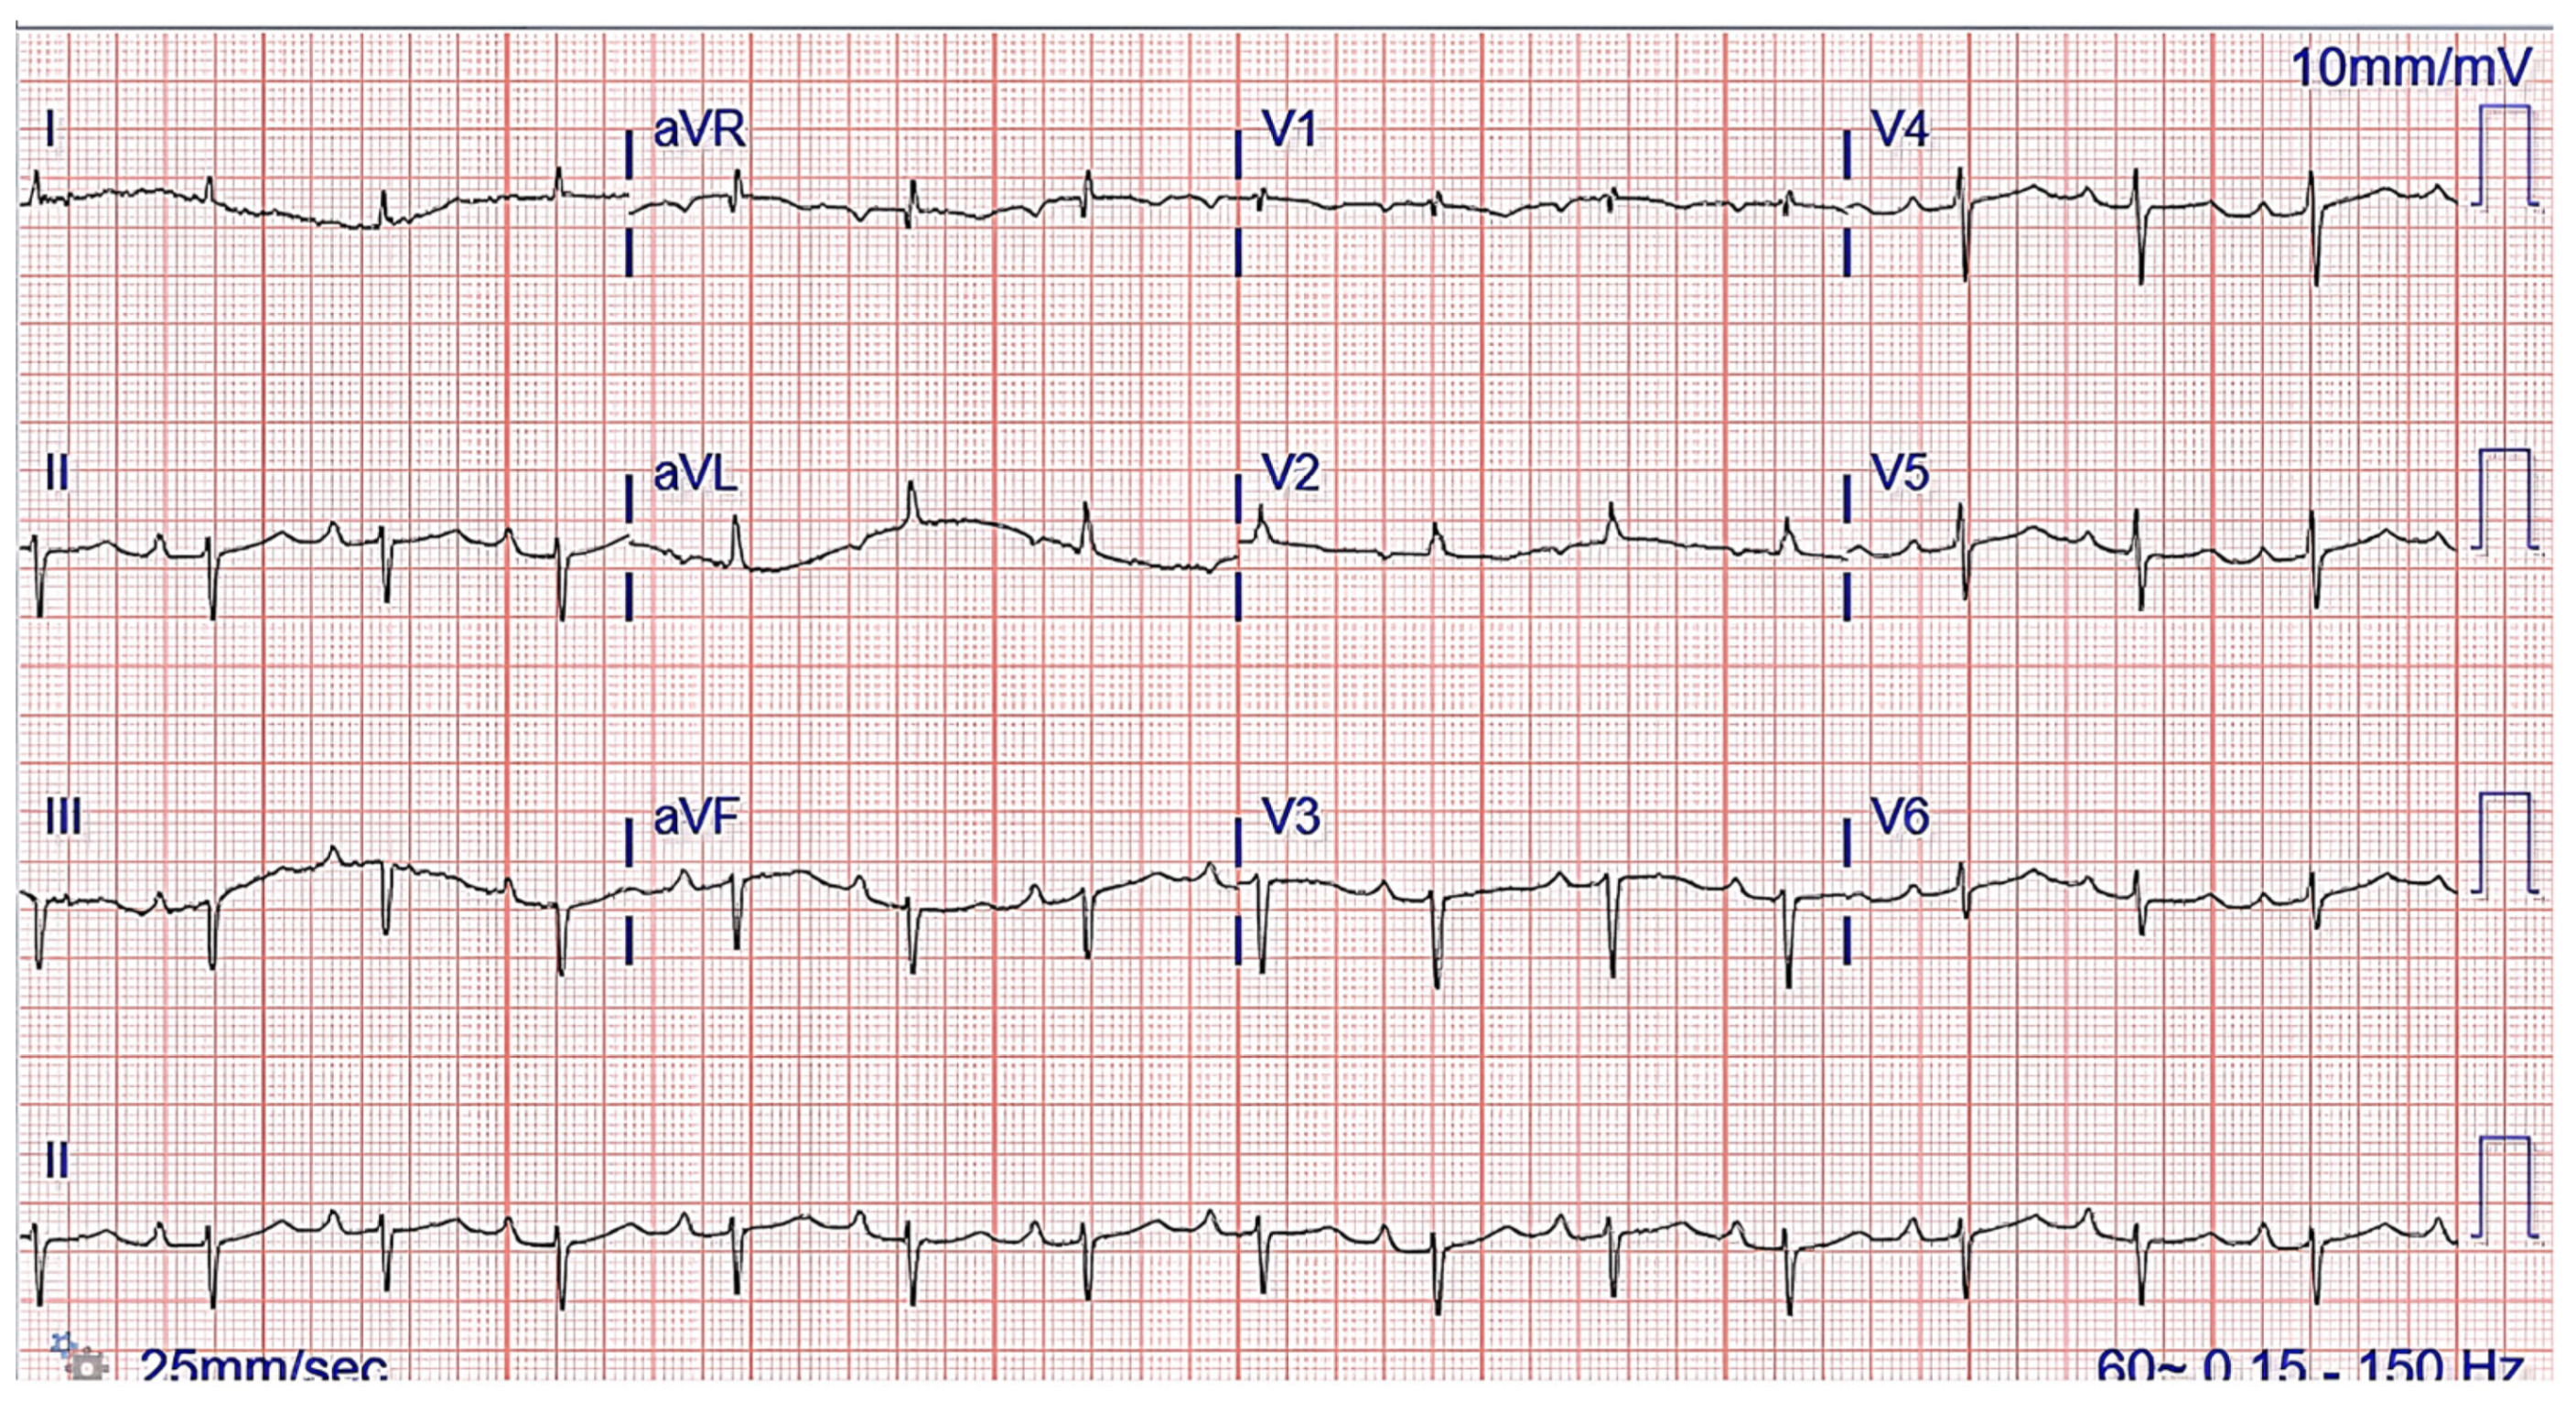

The chest radiograph did not show any acute findings. Electrocardiogram (ECG) (Figure 1) showed normal sinus rhythm with first-degree atrioventricular block, left axis deviation, and low voltage in limb leads. No prior echocardiogram (ECHO) was available, so an initial ECHO was obtained showing preserved ventricular ejection fraction (EF), moderate left ventricular hypertrophy (LVH), stage II diastolic dysfunction, and small pericardial effusion (Figure 2 and Figure 3).

One of the first clues of suspected CA is the EKG. A characteristic ECG finding in CA is low voltage QRS in all limb leads (as amyloid fibrils are electrically silent) and poor R wave progression or a pseudoinfarct pattern with Q waves in precordial leads [32]. This is incongruent with the typical finding of ventricular thickening seen on echocardiography (ECHO). However, with only 30–70% of patients meeting low voltage criteria on EKG, its absence cannot preclude a diagnosis of CA [2]. Other common ECG findings are AF, intraventricular conduction delays, various atrioventricular blocks, and bundle branch blocks.

Figure 1. ECG showing normal sinus rhythm with first-degree atrioventricular block and left axis deviation.